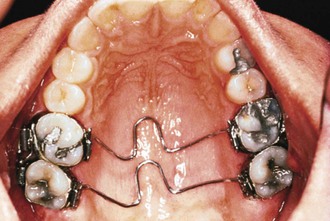

The appliance consists of a palatal acrylic button that is about 25-mm in diameter with distalization springs made of 0.032-inch beta-titanium wire that originate from the palatal acrylic and are engaged in lingual sheaths on maxillary first molar bands (Fig. 12-9). It is bonded to the first and second premolars with wires embedded in the acrylic. It needs only a one-time activation of 60 to 70 degrees, producing a force of 230 g per side. It produces a swinging arch, or pendulum of force, from the palate to the molars. A loop within each spring can be adjusted to allow for expansion and prevent any tendency for the maxillary molar to move lingually into a crossbite. Once the molars are distalized, they may be stabilized with a Nance button attached to the maxillary first molars, a headgear, or a fixed appliance, along with a maxillary utility archwire or a stopped continuous archwire. Usually after molar distalization, the second premolar is released from the anchor unit and allowed to drift distally. According to Hilgers,28 it is not unusual to see as much as 5-mm of distal molar movement in 3 to 4 months of treatment with this appliance.